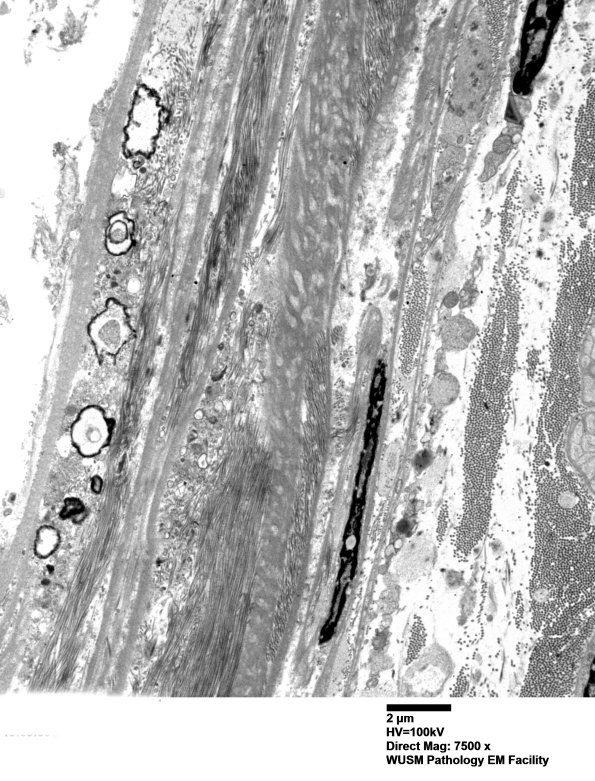

Case 13 History ---- The patient is a 30-year-old pregnant woman with diabetes, weakness, cramping and burning paresthesias in bilateral lower extremities. Electrodiagnostic testing showed a patchy, multifocal, axonal polyneuropathy. CSF studies showed slightly increased protein and normal cell count. There was clinical concern for CIDP or mononeuritis multiplex. Operative procedure: Left quadriceps muscle biopsy; left sural nerve biopsy. ---- Not shown: Toluidine blue stained plastic sections show active Wallerian degeneration involving most myelinated axons with a few remaining smaller myelinated axons. ---- 13A1-3 The perineurium shows numerous focal calcifications of unknown pathogenesis. (electron micrographs)